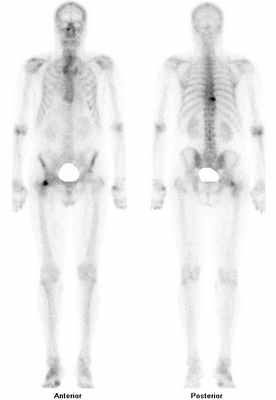

• Костная сцинтиграфия:

о Усиление метаболизма костной ткани

- Сцинтиграфия костей скелета (остеосцинтиграфия, сканирование костей);

- ОФЭКТ/КТ костей скелета;

Сцинтиграфия костей скелета – метод диагностики остеобластических костных метастазов преимущественно при раке молочной железы и раке предстательной железы, а также бластических метастазов других злокачественных новообразований. Визуализация костей осуществляется благодаря использованию меченных технецием-99м фосфатов, тропных к минеральному компоненту костной ткани.

Показания к исследованию: диагностика костных метастазов при первичном стадировании у пациентов высокого риска, оценка эффективности лечения, в т.ч. лучевой и радионуклидной терапии, диагностика прогрессирования, в т.ч. при росте онкомаркеров.